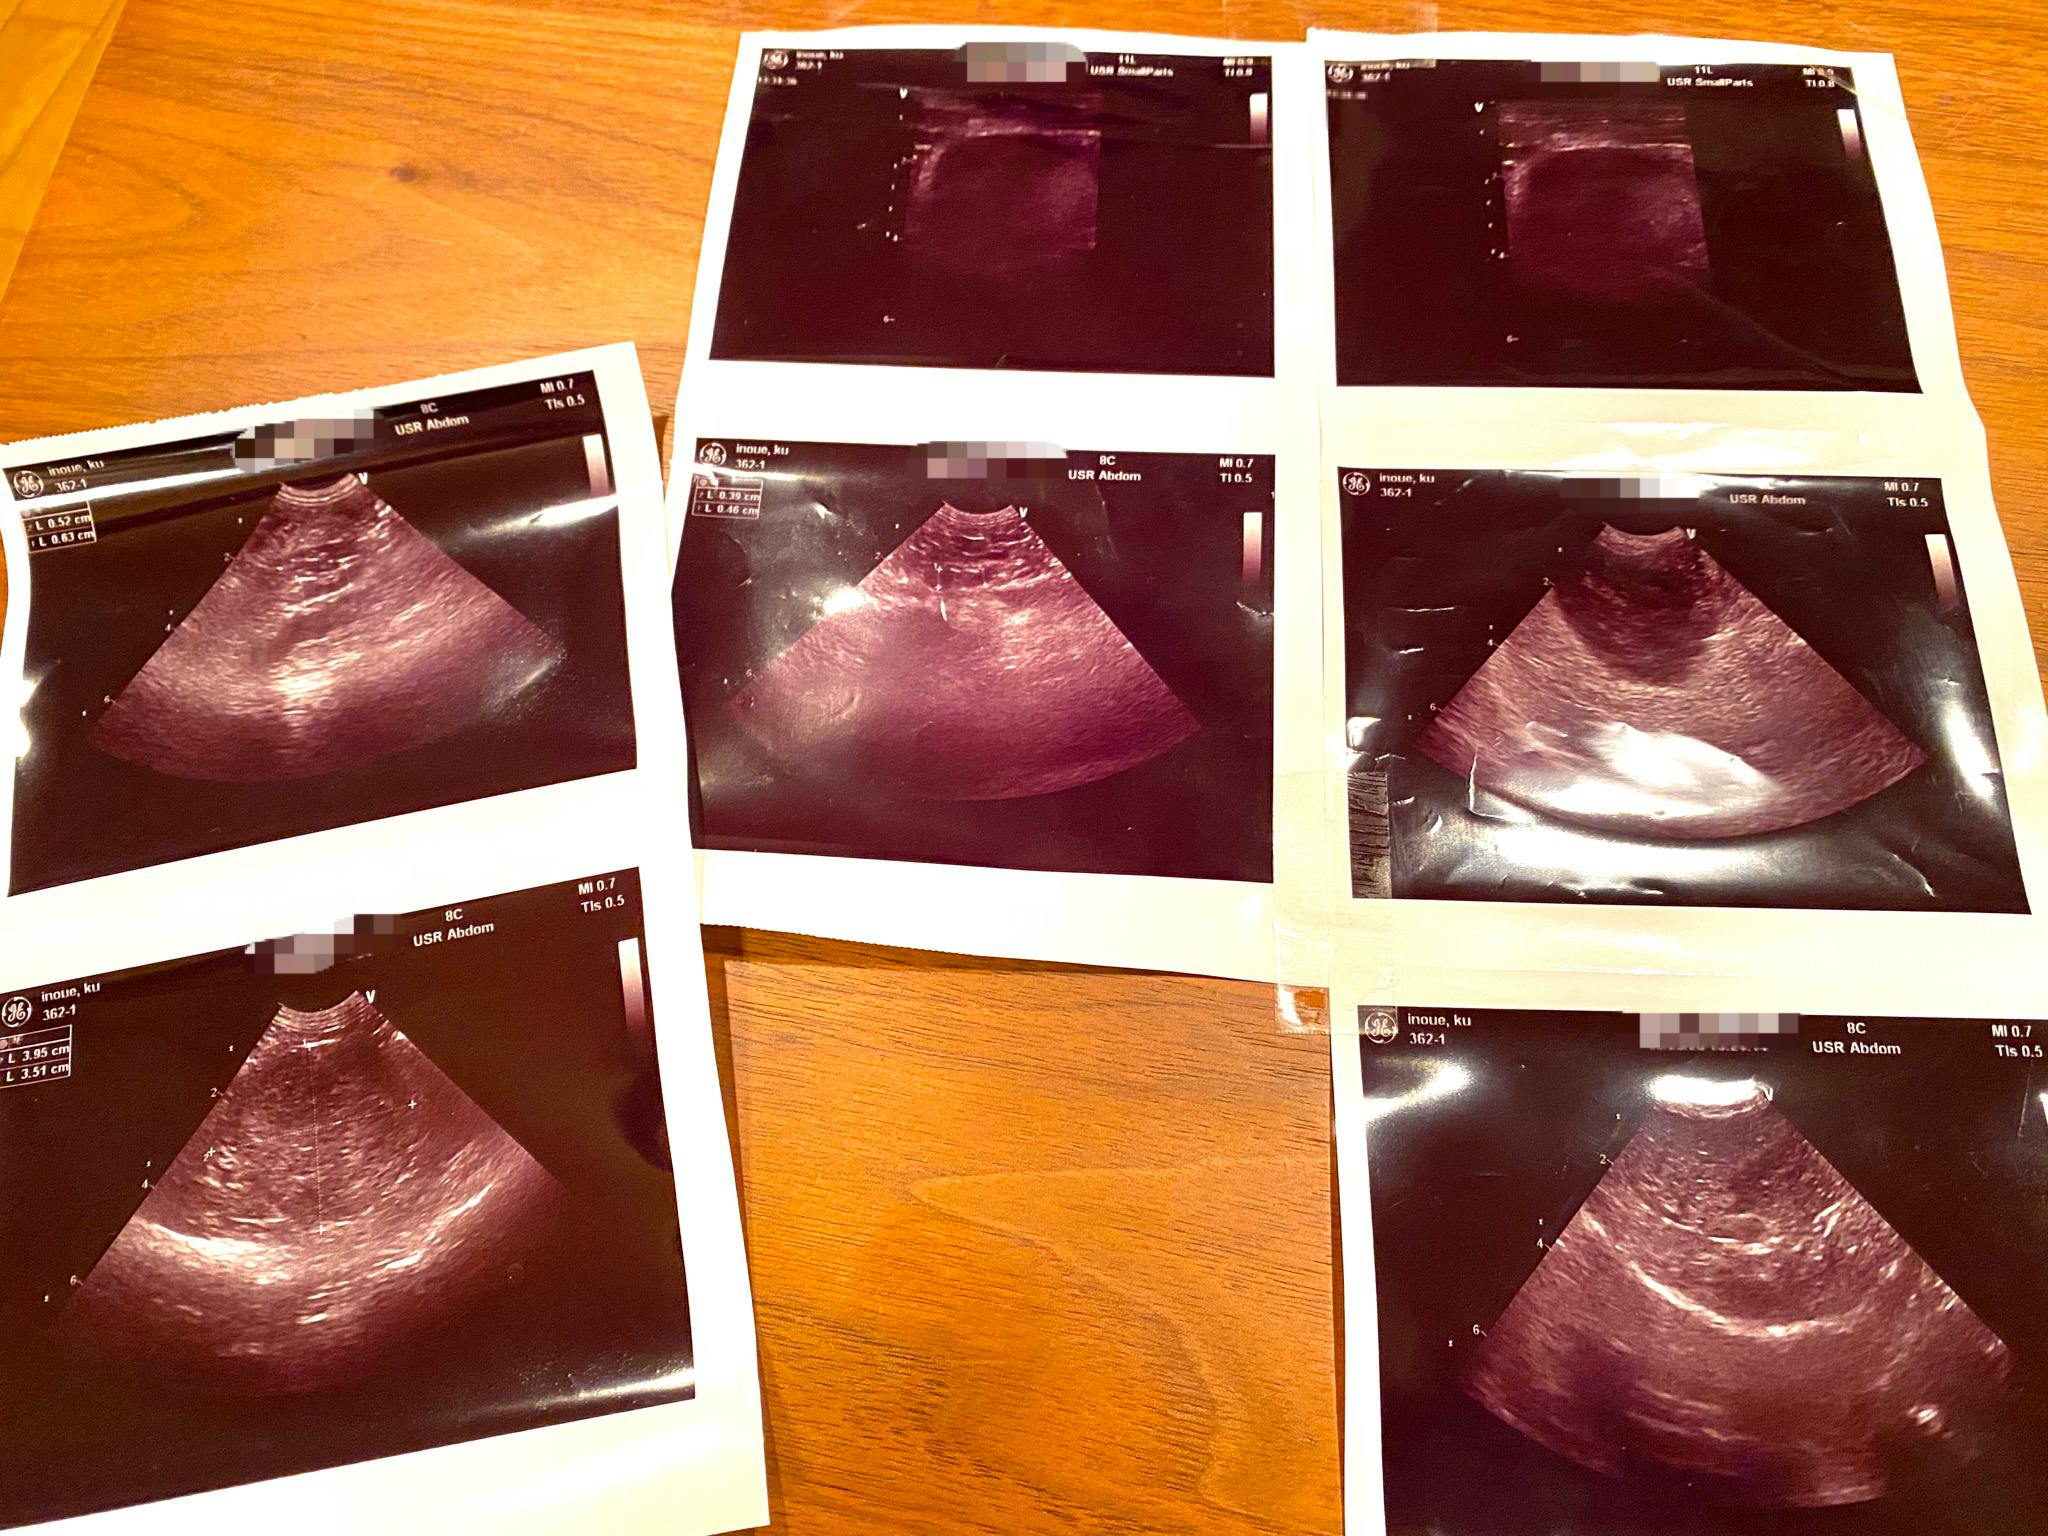

しかし、今年2020年の9月に入り、再び多飲多尿・異常な食欲といった症状が現れ、動物病院にて受診したところ、再度クッシング症候群と診断されました。エコー検査により副腎を除去した箇所に腫瘍がみられるとのことです。

以下は診療明細の一部です。